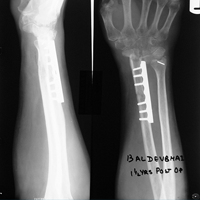

Case:1 GCT L/E Radius

Pre-Op

One and Half month follow up

One and Half year foll

2 years Follow-Up